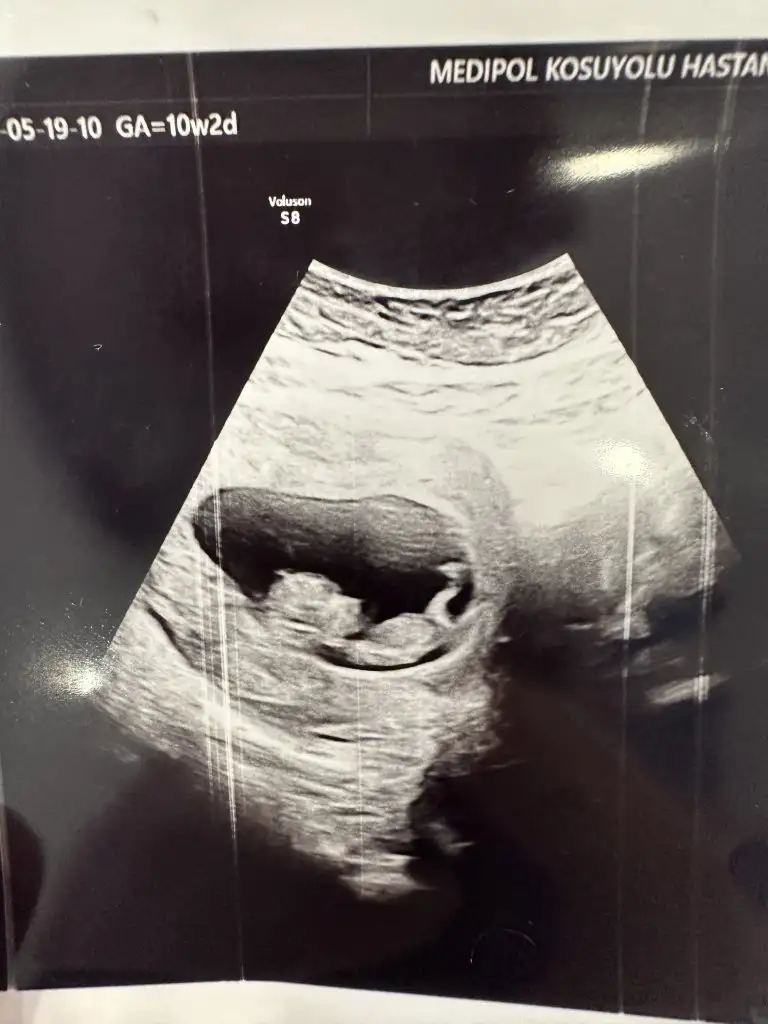

Arkadaş cevapladı mı henüz görmedim ama evet ultrasonda gözüküyor özellikle vajinal ultrasonda daha net belli oluyor . Benim de kanamam varken vajinal baktılar bebiş zıp zıp zıplıyorduhareketli oldugunu ultrasonda mi gosteriyor doktor

10 haftada tum bedeniyle zipliyor kurbaga gibi :) ama 11. Haftadan sonra artik kollarini bacaklarini bagimsiz oynatmaya basliyor. Yavas yavas bir insana benziyor cok heyecanliArkadaş cevapladı mı henüz görmedim ama evet ultrasonda gözüküyor özellikle vajinal ultrasonda daha net belli oluyor . Benim de kanamam varken vajinal baktılar bebiş zıp zıp zıplıyordu

Tam olarak anlamayarak kız diyorumHerkese meraba kızlar bugün kontrol randevum vardı 10+2 yiz normalde ultrasonda 11 haftalık çıktı, cinsiyet tahmini olan varmıdır

Amin inşallah hepimiz sağlıkla kucağımıza alalım bebeklerimiziTam olarak anlamayarak kız diyorumtahmin, sağlıkla kucağınıza alın